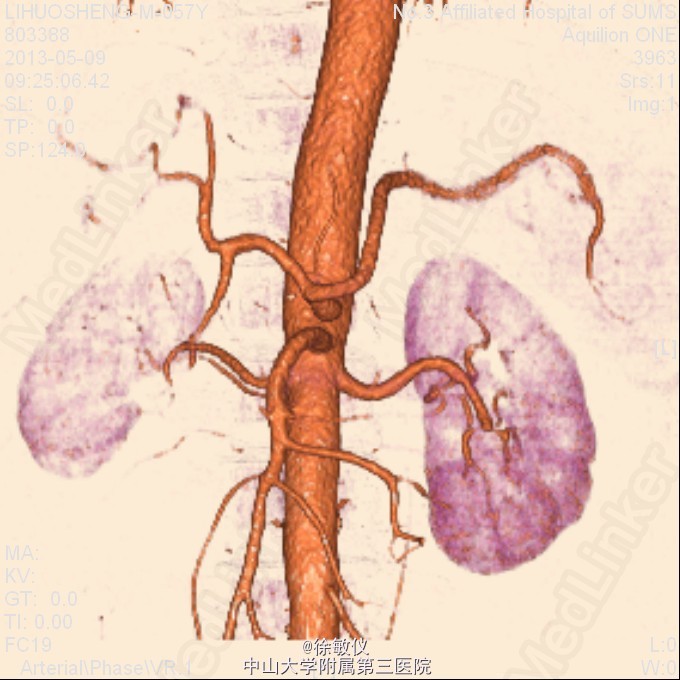

看图片,你的诊断是什么?

老年男性,发现血压升高1年余。平素有降压治疗,但血压控制欠佳,血压最高210/110mmHg,平时血压波动在160-190/90-110mmHg。